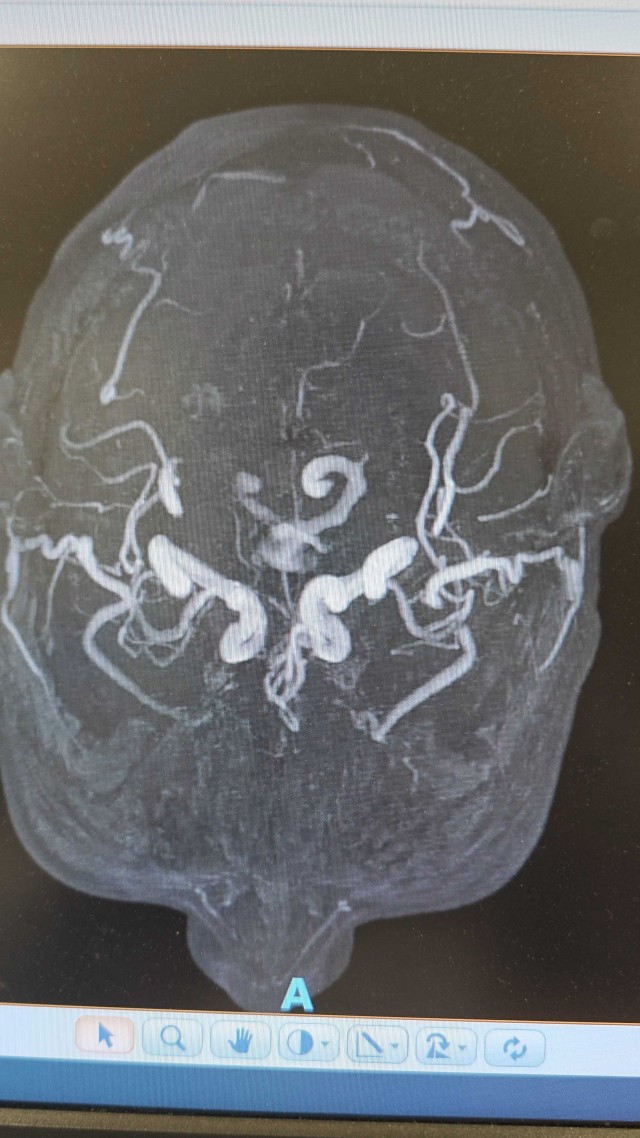

白某某,女性,73岁,2024年01月09日入院。主诉:进展性双下肢无力15天现病史:15天前(12月26日7:00)无明显诱因突发双下肢无力,可缓慢行走,(12月26日9:00)渐进行性加重,双下肢抬离床面困难,不能行走,伴双下肢感觉障碍,小便困难及大便失禁,持续性,无头痛、眩晕、恶心、呕吐,无意识丧失、肢体抽搐、口吐白沫、双眼凝视,偶有口角流涎,无言语含糊、饮水呛咳、吞咽困难。立即就诊于当地县人民医院,因起病急,症状重,病情进展快,双下肢感觉障碍,尿便障碍,短时间内诊断困难,当天转诊于某大学附属医院神经外科,按双下肢无力待查:胸髓缺血诊治后好转,双下肢较前有力,可借助外物缓慢挪步,行走不稳

coverplay

病例 · 319 浏览 · 4 讨论